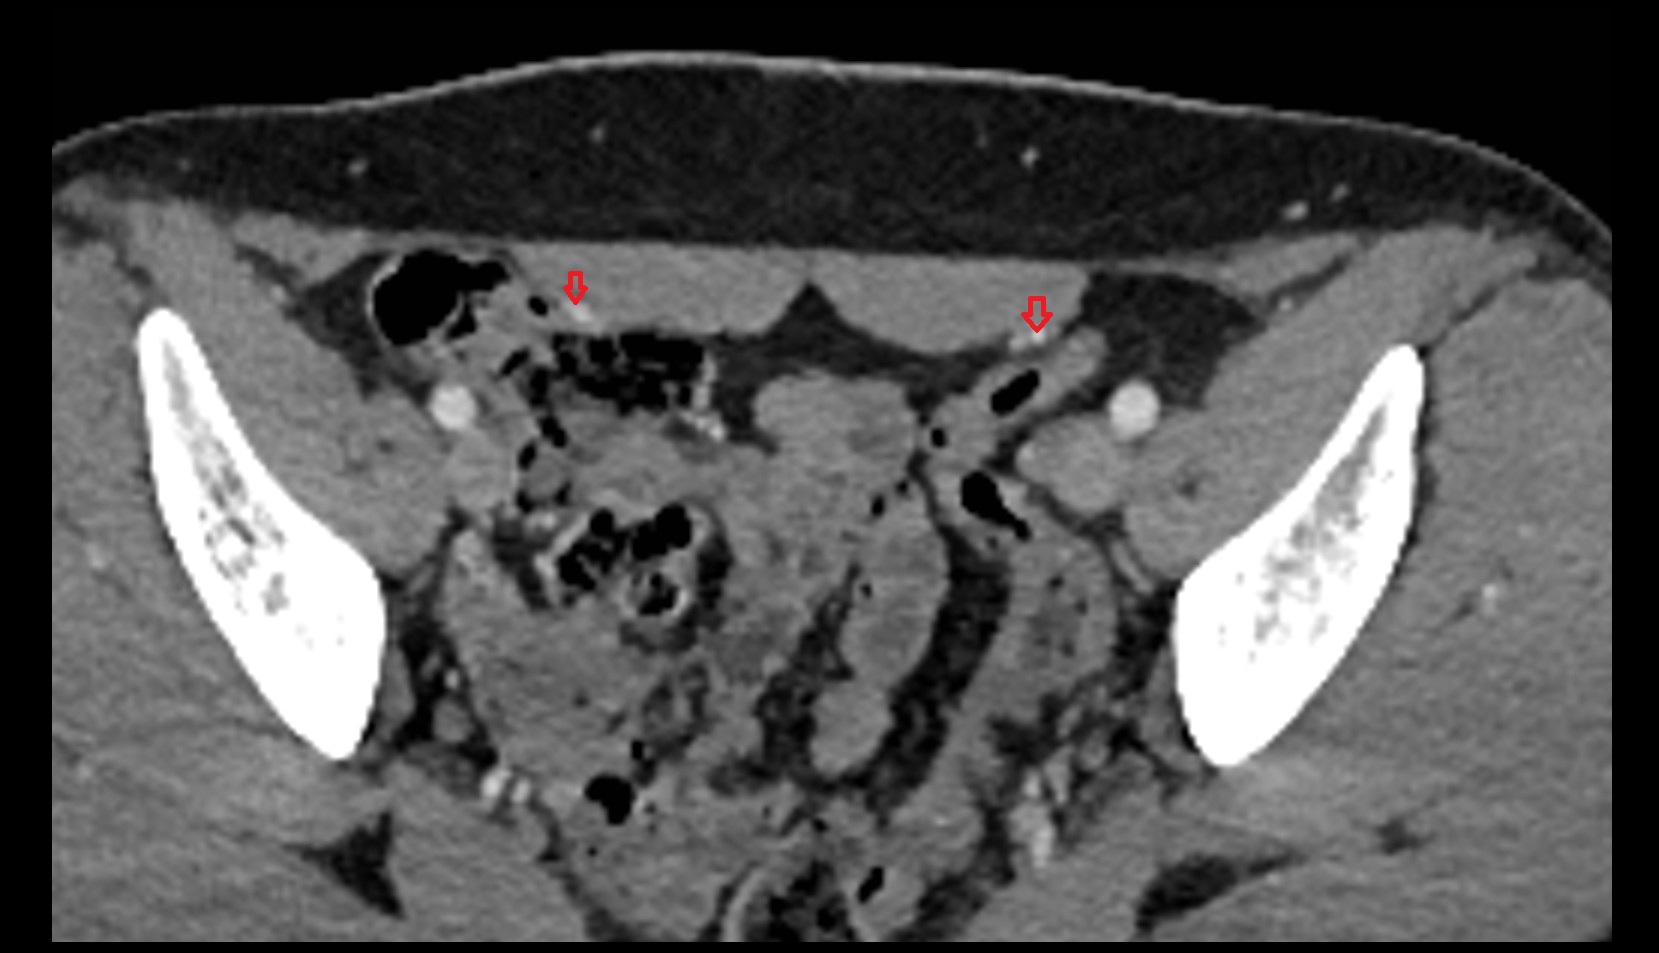

- Inguinal lymph nodes